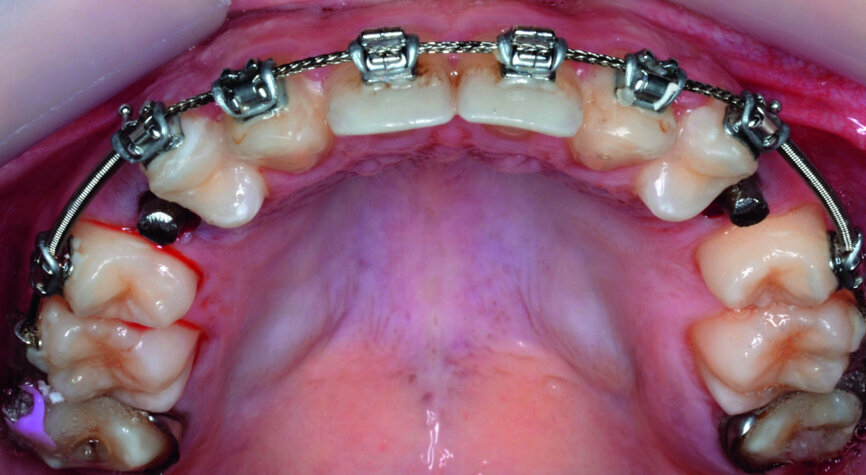

- Upper bracket placement (Fig. 22): level and align the gingival margins, and correct the torque on the upper canines who will substitute the lateral incisors.

- Implants space opening: substitute laterals with canines (Figs. 23–25) and substitute canines with first premolars (Figs. 26–28).